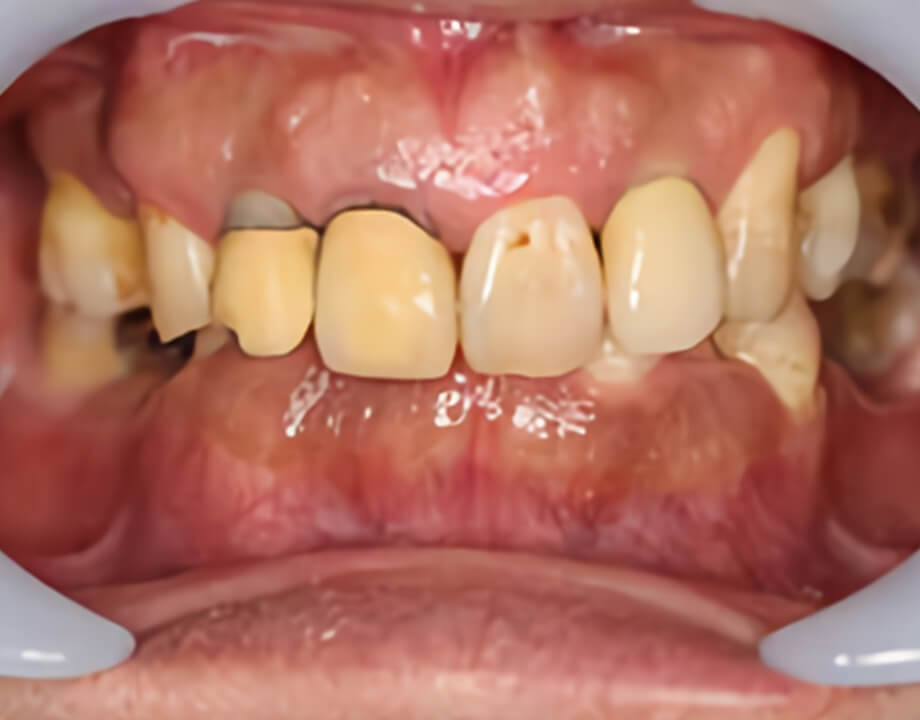

Case 01天然歯

ジルコニアレイアリング

Case 07咬合再構成

アナログワックスアップ

→シュミレーション(ノーベルガイド)

→プロビジョナル(即時荷重)

→最終補綴物(ハイブリッドクラウン)